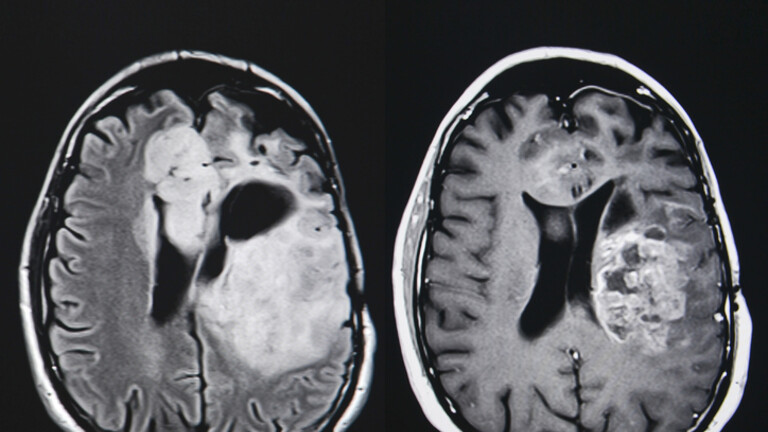

Tumor na mozgu, ilustracija

Tumor na mozgu, ilustracija (Foto: Getty Images)

Glioblastom je maligni tumor koji brzo raste, potiskuje imunološki odgovor i nastaje duboko u mozgu. Oštećuje tkiva izazivanjem oticanja, pritiskom i smanjenjem dotoka krvi.